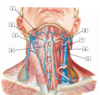

A

16

2

2 - retromandibular vein

Q

A

18

4

4 - anterior jugular vein

Q

A

20

6

6 - internal jugular vein

#7

30

#8 - transverse cervical artery

#9

31

#1 - superficia temporal artery

#2

33

#3 - internal carotid artery

#4

35

#5 - common carotid artery

#6

37

#7 - ascending pharyngeal artery

#8

39

#9 - facial artery

#10

41